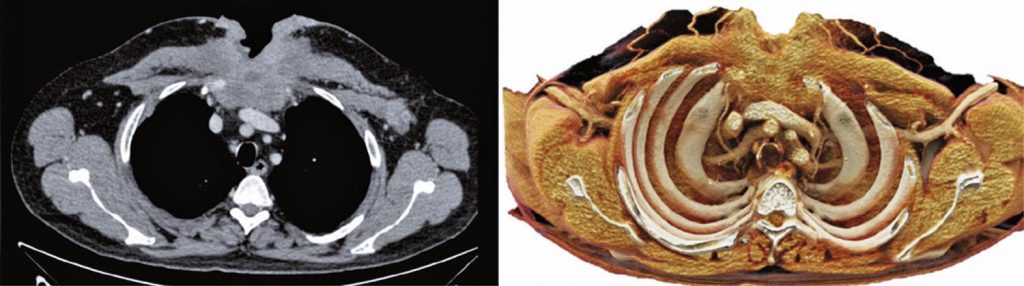

Uma nova realidade: renderização cinematográfica para reconstruções tridimensionais da parede torácica

A tomografia computadorizada com os múltiplos detectores e o avanço dos processadores melhoraram as imagens renderizadas e as reconstruções tridimensionais na prática clínica. Os cortes axiais tradicionais formam imagens não intuitivas, pois são vistas em apenas um plano. Já as reconstruções tridimensionais podem exibir detalhes anatômicos em diferentes perspectivas das estruturas e de doenças com anatomia complexa. A renderização cinematográfica é uma técnica de reconstrução tridimensional recentemente introduzida, já aprovada para uso clínico, que pode produzir imagens realistas a partir de dados tradicionais da tomografia computadorizada. O algoritmo usado é baseado em métodos de trajetória da luz e no modelo de iluminação global, os quais simulam milhares de imagens de todas as direções possíveis. Assim, a técnica molda a propagação física da luz e gera uma imagem tridimensional realista, com profundidade, sombras e mais detalhes da alteração anatômica. É uma renderização multidimensional adquirida por efeitos de iluminação complexos. O objetivo deste artigo foi mostrar o avanço da tecnologia tridimensional com a renderização cinematográfica nos dos exames de imagens da parede torácica.